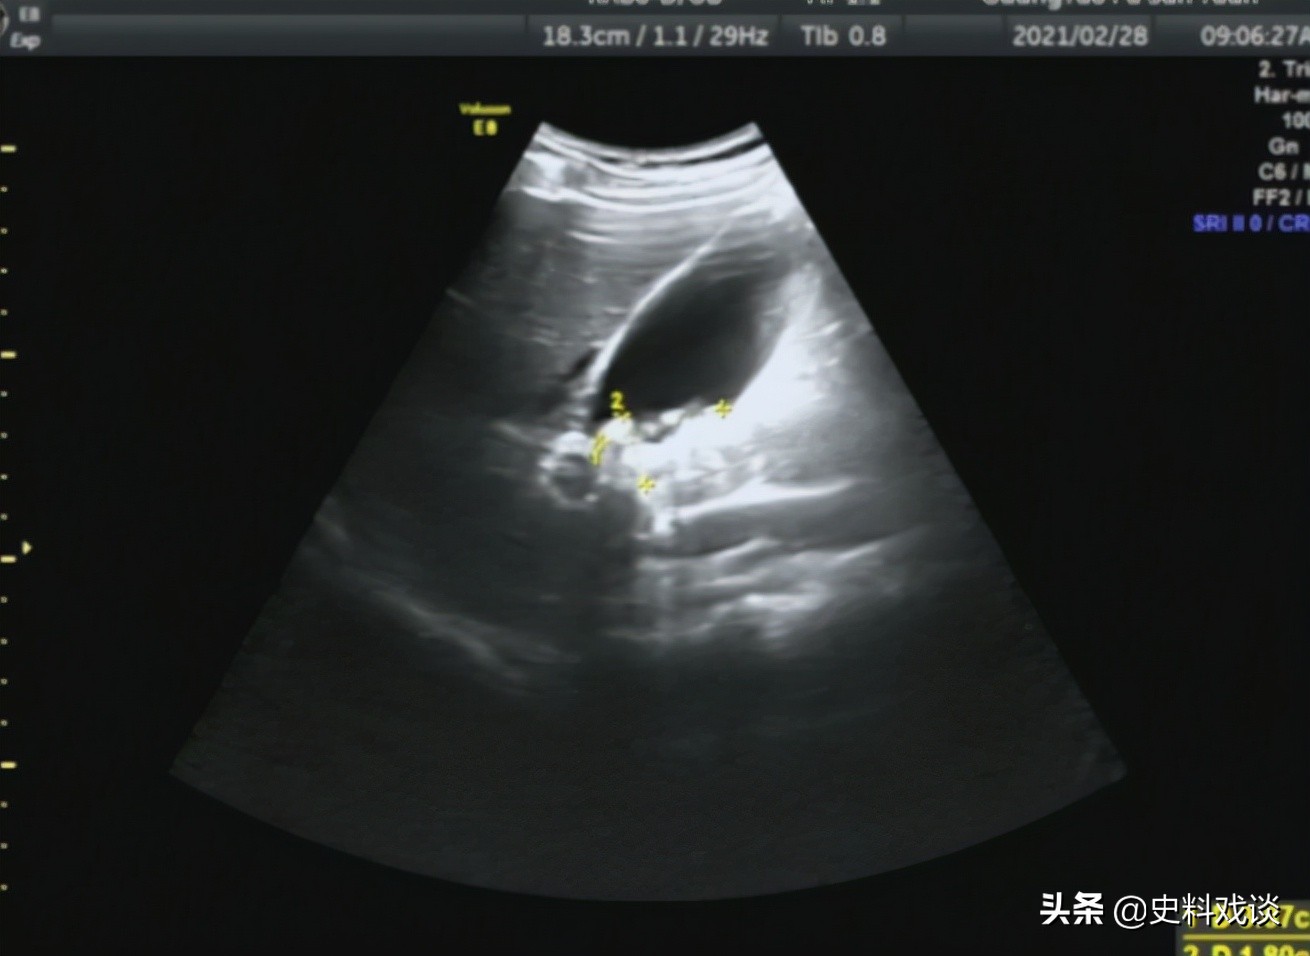

原来, 过年前 陈美因胆结石住院做手术 ,在外地的丈夫又还没回来, 自己就发了个朋友圈。 没想到看到她的朋友圈的不但有现任,还有前任。

胆结石

杨林说婚前没说她胆结石,结了婚以后才说,手术费是他出的,跟他结婚就是为了手术费。

“胆结石手术才几个钱?我开棋牌室差这点钱?非得跟你结婚才能治?”